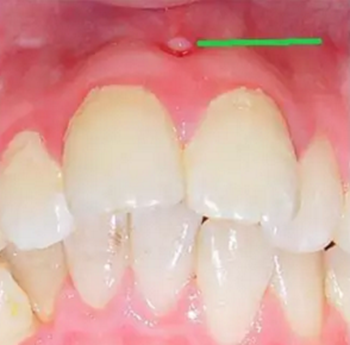

第五步:急性根尖周炎

當(dāng)您臉腫得睜不開眼睛時,您撐著眼睛說:“沒什么大不了的,吃吃消炎藥就好了。”

牙醫(yī)卻著急地說:“牙齒急性根尖周炎感染可能引起間隙感染,嚴(yán)重的會危及生命。此時,需要到正規(guī)牙科治療患牙,配合藥物治療,必要時做膿腫切開引流術(shù)。”